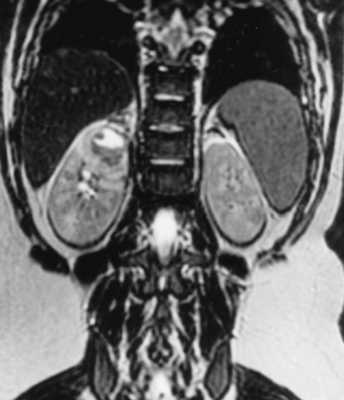

Женщина, 70 лет; страдает сахарным диабетом. Боли в поясничной области, лихорадка. На представленных Т1 постконтрастных изображениях в корональной (А) и сагиттальной (б) плоскостях визуализируется клиновидной формы участок пониженного контрастирования в верхнем полюсе правой почке.

Т1 с контрастным усилением: линейные или клиновидные участки пониженного накопления контрастного вещества

МРТ при пиелонефрите

Пиелонефрит - инфекция почек, возникающая в чашечно-лоханочной системе и паренхиме. Возбудителем является бактериальная инфекция, в том числе туберкулезная. Очень редко встречается грибковый пиелонефрит. Клиническая симптоматика острого пиелонефрита типична: острое начало с лихорадкой, боли в пояснице. Увеличение количества лейкоцитов и наличие бактерий в моче подтверждает диагноз. Попадает инфекция в почки ретроградным путем из нижних мочевых путей, а затем распространяется через чашечно-лоханочную систему в паренхиму почек, нарушая микроциркуляцию крови и приводя к ишемии. Обычно после клинического обследования пациентам назначают УЗИ, при котором лишь изредка удается найти изменения - локальные нарушения эхогенности паренхимы, скопления газа при эмфизематозном пиелонефрите и участки сниженной васкуляризации коры при дуплексном исследовании. Наиболее полезен метод при осложненном пиелонефрите - абсцессе, гидронефрозе, инфаркте почки. КТ без контрастирования также малочувствительна. После введения контраста при КТ можно увидеть участки отека со снижением плотности, между медуллярным и кортикальным веществом почки появляется полоска сниженного контрастирования (“кортикальный ободок”). Отмечается длительная задержка контраста в почке. При МРТ почки пиелонефрит проявляется в виде гиперинтенсивных участков на Т2-взвешенных МРТ. Также отмечается сниженное накопление контрастного вещества в пораженных участках при МРТ с контрастированием. Осложнениями острого пиелонефрита являются абсцесс ( при его прорыве с пиелонефрозом) и инфаркт почки. Изменение сигнала на диффузионно-взвешенных МРТ неспецифично, так как наблюдается и при почечно-клеточном раке.